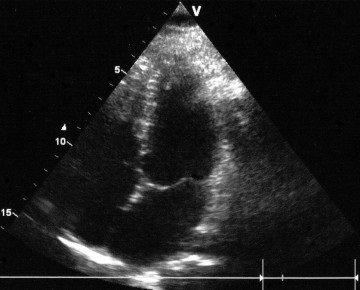

Itt egy tipikus kép egy négykamrás szakaszról, amely szerint az oroszországi echokardiográfusok többsége egyértelműen előidézi a prolapsus MK-t:

Ha a bal szívét vázolja, az orosz doktor-echokardiográfus szokásos akciói a következők:

Tartott egy egyenes vonal a bázis a szélén a elülső betegtájékoztató a mitrális billentyű (PSMK), majd a mért milliméterben elhajlást központ és abban következtetést a jelenléte a beteg elülső betegtájékoztatót előesés MK és annak mértékét.

Süllyedés, vagy megereszkedett, az egyik vagy mindkét mitrális szisztolés fázis alatt tartják igaz csak akkor, ha be van jegyezve két echokardiográfiás helyzetben :. Apical négy kamra és parasternalis a hosszanti tengelye mentén a bal kamra „End quote.

Itt van a kutya eltemetve, kedves kollégák, echokardiográfusok. A parasternal helyzetben az úgynevezett "prolapsusok" 99% -a azonnal levágódik.

Gyakran láttál ilyen képet egy parasternal helyzetben? Nem.